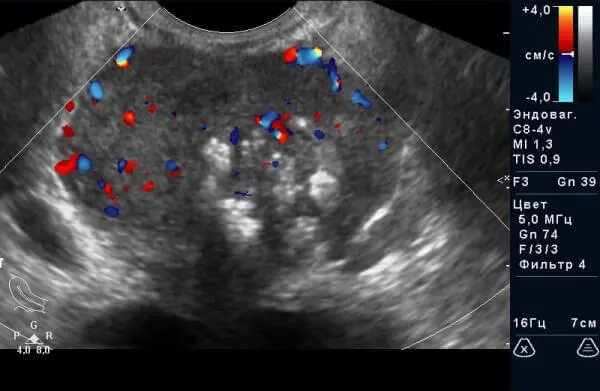

Рис.1 Рак передміхурової залози у вигляді кальцинованого ділянки з деформацією контурів і асиметрією.